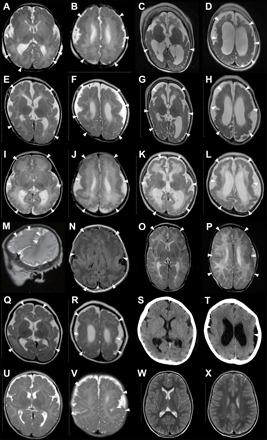

新发ATP1A3变异导致多小脑回畸形。

De novo ATP1A3 variants cause polymicrogyria.

Polymicrogyria is a common malformation of cortical development whose etiology remains elusive. We conducted whole-exome sequencing for 124 patients with polymicrogyria and identified de novo variants in eight patients. Mutated causes functional brain diseases, including alternating hemiplegia of childhood (AHC), rapid-onset dystonia parkinsonism (RDP), and cerebellar ataxia, areflexia, pes cavus, optic nerve atrophy, and sensorineural deafness (CAPOS). However, our patients showed no clinical features of AHC, RDP, or CAPOS and had a completely different phenotype: a severe form of polymicrogyria with epilepsy and developmental delay. Detected variants had different locations in and different functional properties compared with AHC-, RDP-, or CAPOS-associated variants. In the developing cerebral cortex of mice, radial neuronal migration was impaired in neurons overexpressing the variant of the most severe patients, suggesting that this variant is involved in cortical malformation pathogenesis. We propose a previously unidentified category of polymicrogyria associated with abnormalities.

摘要

多小脑回是一种常见的皮质发育畸形,其病因尚不清楚。我们对124例多小脑回患者进行了全外显子组测序,在8例患者中鉴定出新生变异。突变导致功能性脑部疾病,包括儿童交替性偏瘫(AHC)、快速发作性肌张力障碍帕金森综合征(RDP)以及小脑性共济失调、无反射、弓形足、视神经萎缩和感音神经性耳聋(CAPOS)。然而,我们的患者没有AHC、RDP或CAPOS的临床特征,而是具有完全不同的表型:一种伴有癫痫和发育迟缓的严重多小脑回形式。与AHC、RDP或CAPOS相关变异相比,检测到的变异在位置和功能特性上有所不同。在小鼠发育中的大脑皮质中,过表达最严重患者变异体的神经元的放射状神经元迁移受损,这表明该变异体参与了皮质畸形的发病机制。我们提出了一种先前未被识别的与异常相关的多小脑回类型。